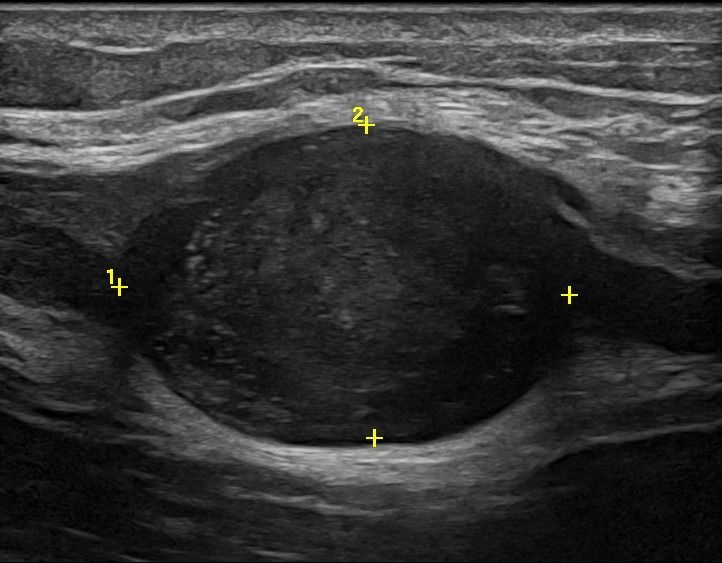

- Focal Lesions (tumors, neuromas)